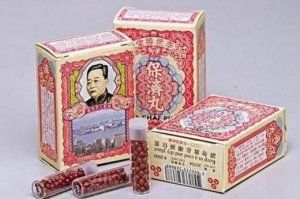

更新时间:2019-05-14标签:最佳医院医院学科全文阅读 香港必买的42种好药 赶紧收藏,别在乱买

香港必买的42种好药 赶紧收藏,别在乱买

导语:香港作为购物的天堂,各类上商品可以说是应有尽有,除了护肤品、奢侈品,香港当地还有很多的药品是适合买的,那么香港到底有哪些必要药呢?下面排行榜123网就整理了香港必买的...

更新时间:2019-05-14标签:香港旅游全文阅读 到澳门必买的十样药品 你买的是这些吗

到澳门必买的十样药品 你买的是这些吗

导语:相信很多人去澳门有很大一部分原因是为了购物,而当地种类多样的商品市场也满足着人们的需求,那么在澳门的药品市场上有哪些是不得不买的呢?下面排行榜123网就整理了到澳门必买...